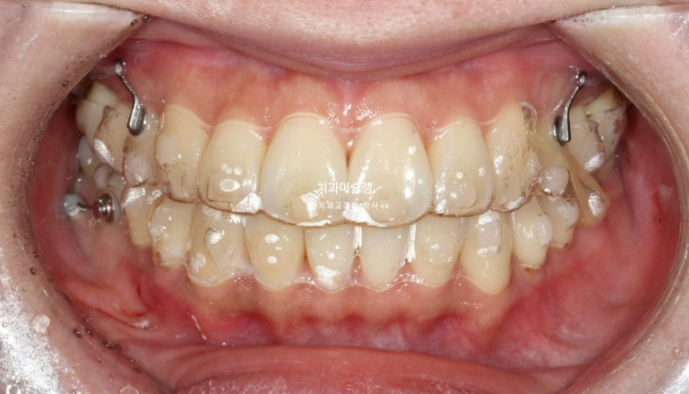

24년 8월까지 일년간 첫세트 48개 장치를 모두 낀 후 모습입니다.

24.08

중심선 불일치가 아직 조금 남았고, 가위교합은 모두 해소가 되었습니다.

앞니 뻗침도 개선이 되었고, 어금니 교합도 좋습니다.

혀쪽으로 쓰러져 있던 아래 큰어금니도 잘 섰습니다.

모든게 좋지만 앞니 돌출감을 추가적으로 더 개선하고자, 사랑니 공간 이용 전체치열 후방이동을 한세트 더 하기로 합니다.